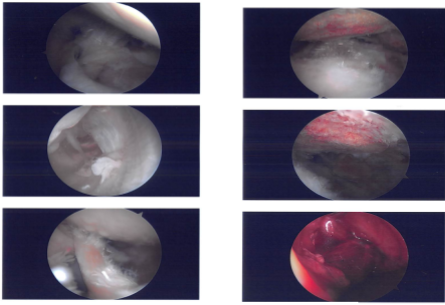

The arthroscope was made from the posterior soft spot. Biceps tendon, intra articular portion and the labrum had extensive fraying. Shaver was used for labral debridement. The rotator cuff was intact.

Debridement of subscapularis tendon as well as chondroplasty of the glenoid and humeral head was also performed. Arthroscope was inserted into the subacromial region and a shaver was inserted from the front and debridement with subacromial bursectomy was performed with a shaver. Acromial spurring was present, which was cleaned by the use of Coblation wand and #6.0 bur performing acromioplasty.

The AC joint also showed arthritic changes and so distal clavicular excision was done by excising about a centimeter of distal clavicle with the use of shaver from the posterior anterior portal. Examination of the rotator cuff was performed, which showed partial thickness rotator cuff tear.

It was of low grade and debridement was performed with the use of shaver. Considering the patient’s labile diabetes, it was decided not to use any implant to repair further. The final pictures were saved and the arthroscope was removed.

Intraoperative Images